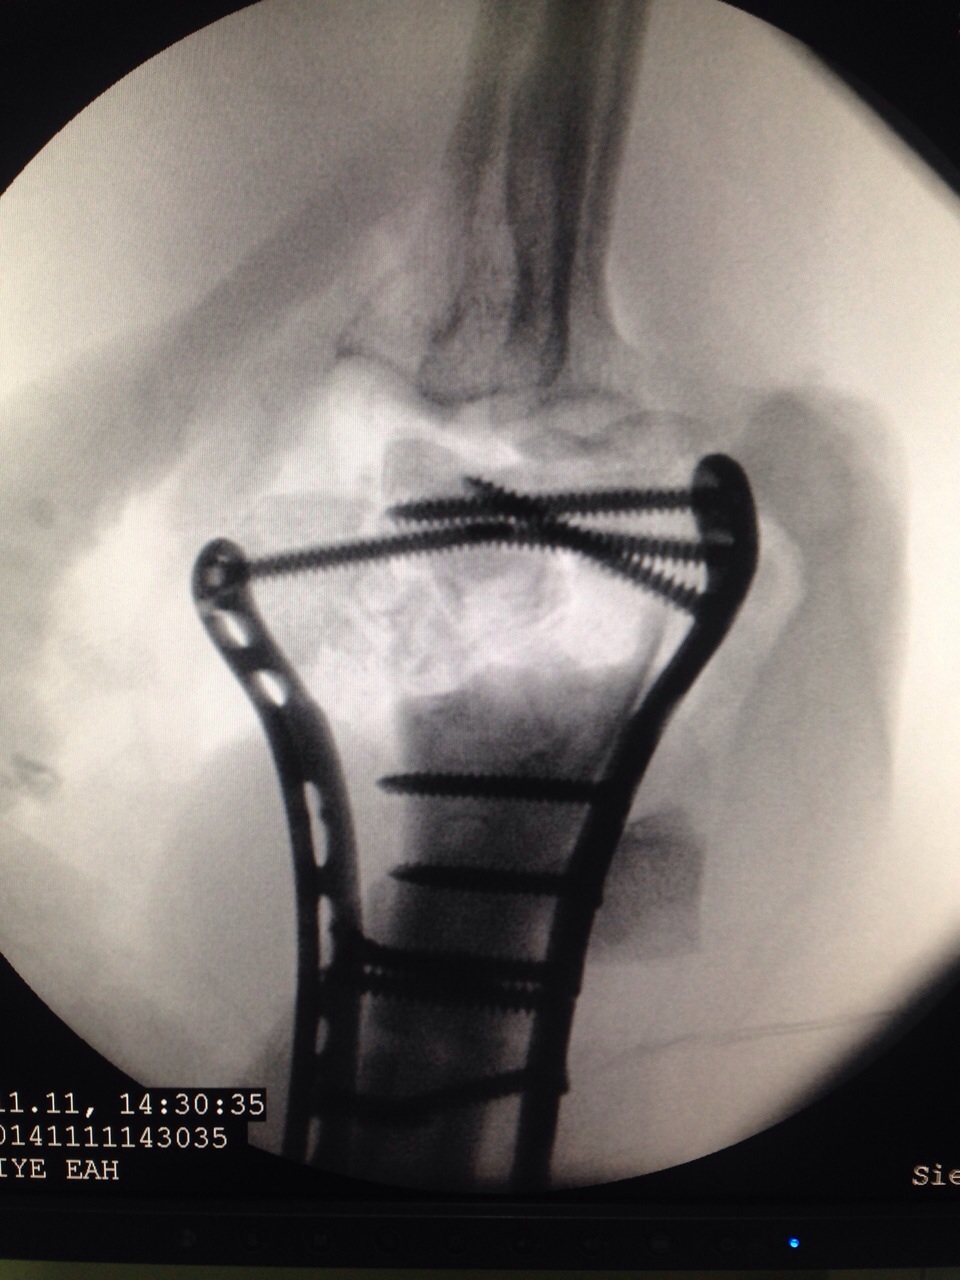

Images Gallery